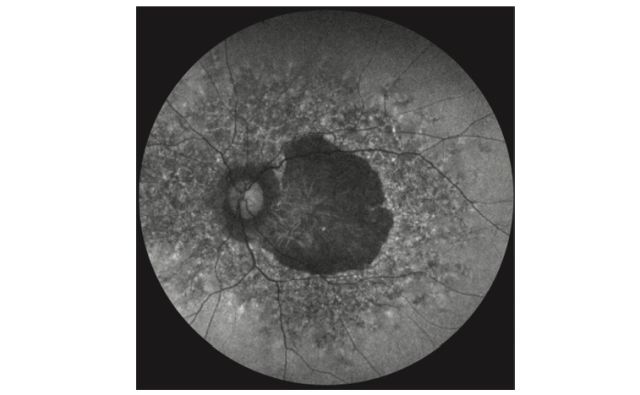

🔒 Phase-II-Studie zur Behandlung geografischer Atrophie gestartet